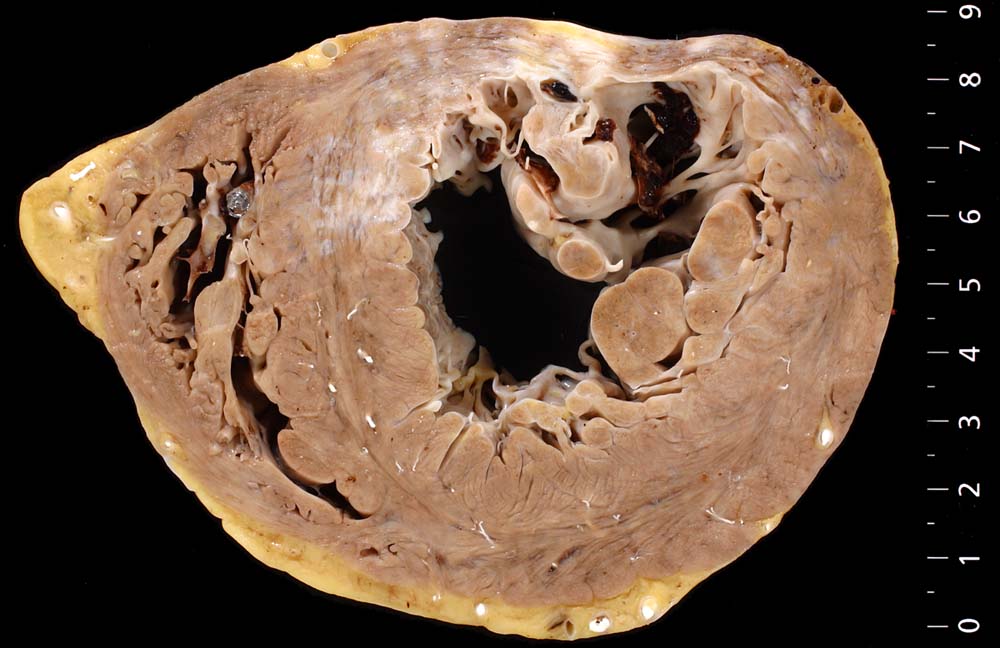

Komplikationen:

Im Bereich grösserer Narben ist das Myokard verdünnt. Bei 8% der transmuralen Infarkte entsteht im Bereich der Narbe ein Herzwandaneurysma (> 2088) mit oder ohne wandständige Thrombose (> 348). In 5-15% führen die Thromben zu systemischen Embolien. Von der Randzone der Aneurysmen gehen oft hartnäckige ventrikuläre Rhythmusstörungen aus. Grosse Narben führen zu einer Verminderung der Pumpleistung mit Herzinsuffizienz.

Eine restitutio ad integrum nach abgelaufener Myokardnekrose ist nicht möglich. Wird das Ischämieereignis überlebt, kommt es zu einer reparativen Regeneration mit Ersatz der Muskulatur durch kollagenreiches Narbengewebe. Dieser Vorgang setzt etwa ab dem 9. Tag nach Infarkt ein und dauert bis zur vollständigen narbigen Ausheilung bei transmuralem Infarkt etwa 50 Tage. Makroskopisch imponiert die Narbe als fasriges weisses derbes Areal. Von einem Infarkt spricht man, wenn die Nekroseareale einen Durchmesser von mindestens 3cm Durchmesser haben. Ab dieser Grösse kann klinisch das Bild eines Myokardinfarktes ausgelöst werden. Kleinere, makroskopisch sichtbare Narben werden als grobfleckige Myokardfibrose (> 873) (> 234) bezeichnet.